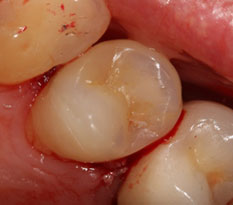

Ко мне обратилась пациентка с просьбой попробовать «спасти» нижний 6-ой зуб от удаления. Вот так он выглядел в полости рта.

Что мы здесь видим? Ну, во-первых, напрочь отсутствующую анатомию зуба. Огромная полость заштукатурена (другого слова и не подберешь) без малейшей попытки создать на зубе необходимый для жевания рельеф поверхности с бугорками и бороздками между ними. Через материал просвечивает анкерный штифт, который призван удерживать эту «нашлепку» внутри зуба. Во-вторых, по краям пломбы заметно прокрашивание границы, т.е. пломба уже давно негерметична, а, значит, внутрь просачивается микрофлора полости рта, вызывая рецедив кариеса и воспалительный процесс в костной ткани вокруг корня. В-третьих, мы можем видеть только 2 сохранившихся стенки собственного зуба, которые к тому же изрядно истончены. Учитывая, что зуб давно мертвый, методика реставрации явно выбрана неудачная. Да и исполнена при этом весьма скверно. Дело в том, что наши жевательные зубы испытывают достаточно серьезные нагрузки при жевании (по разным данным около 100 кг на см2), и оставшиеся тонике стеночки в любой момент могут треснуть. Нередко трещина уходит глубоко под десну и в итоге зуб приходится удалять. Поэтому если зуб депульпирован и имеет значительные разрушения (как в нашем случае), то его нужно обязательно восстанавливать коронкой. Только в этом случае Вы будете застрахованы от любых неприятных сюрпризов. Но для данного зуба это только полбеды. Не меньшая проблема содержалась и внутри.